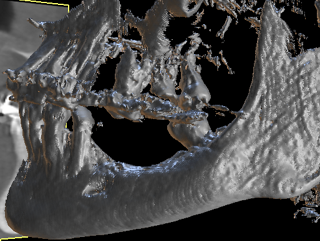

Dr Franck AFOTA, France In this clinical situation, the autogenous split bone block technique offered interesting indications and results in terms of regenerated bone. Read more